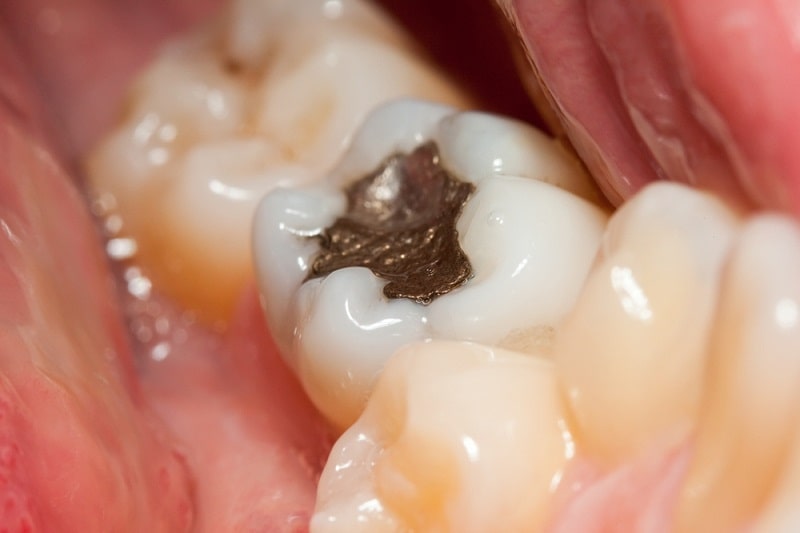

تا چند روز بعد از عصب کشی دندان درد دارد

در طول درمان کانال ریشه دندانپزشک اقدام به برداشتن پالپ عفونی می کند. در یک درمان کامل این عفونت حذف می گردد. در مواردی به دلیل پیچیدگی کانال ریشه دندان و ... احتمال باقی ماندن مقداری باکتری عفونی در کانال ریشه وجود دارد. این باکتری ها سبب می شوند که بافت عفونی شکل بگیرد و درد زیادی ایجاد شود. بدن به صورت خود ایمن برای حذف این عفونت اقدام می کند و آنتی بیوتیک های تجویز شده توسط متخصص نیز برای حذف درد کمک کننده است.